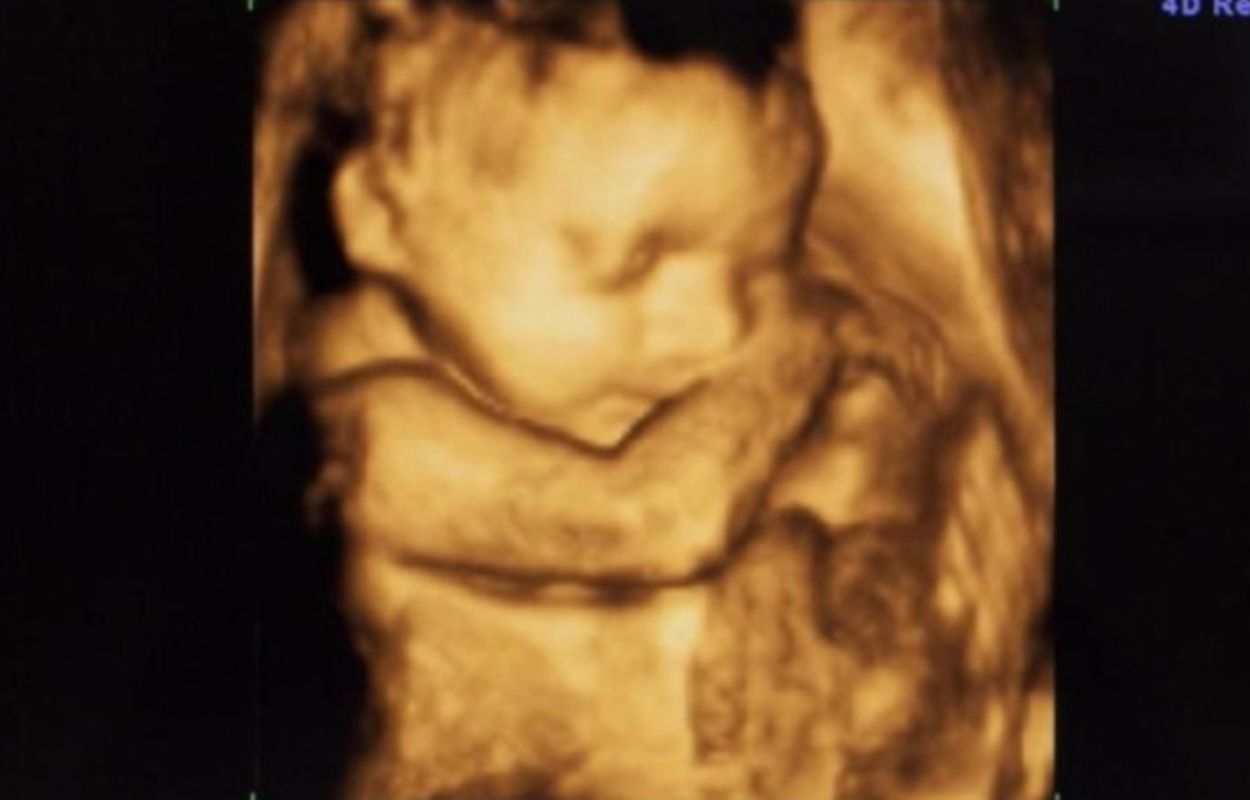

finnews.id – Janin berusia delapan bulan meninggal setelah ibunya, SA (40), meminum obat penggugur kandungan hingga 50 butir di Kelurahan Kramat Jati, Kecamatan Kramat Jati, Jakarta Timur.

“Tersangka SA (40) memutuskan aborsi dengan cara meminum obat hingga 50 butir. Bayi dalam kandungan berusia delapan bulan akhirnya gugur dengan perbuatan tersangka,” kata Kepala Unit (Kanit) Perlindungan Perempuan dan Anak (PPA) AKP Sri Yatmini saat konferensi pers di Mapolres Metro Jakarta Timur, Senin.

Sri menjelaskan SA membeli puluhan obat itu secara daring dan mulai mengonsumsinya sejak awal November 2025. Kasus ini masuk dugaan tindak pidana kekerasan fisik dan atau melakukan aborsi terhadap anak yang masih dalam kandungan.

Petugas juga menemukan sejumlah barang bukti, termasuk jasad bayi yang disimpan dalam sebuah ember.